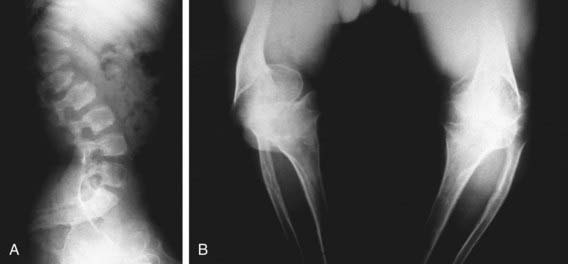

The severity of radiographic changes correlates with the clinical severity (Fig. 686-1). Both conditions produce short, broad tubular bones with cupped metaphyses. The pelvic bones are hypoplastic, and the cranial bones are not well mineralized. The vertebral bodies are poorly ossified in the entire spine in achondrogenesis type II and in the cervical and sacral spine in hypochondrogenesis. The pedicles are ossified in both.

Figure 686-1 Stillborn infant with achondrogenesis type II. Note poor ossification of calvaria, vertebral bodies, and sacrum; hypoplasia of pelvic bones; and short tubular bones with cupped metaphyses.